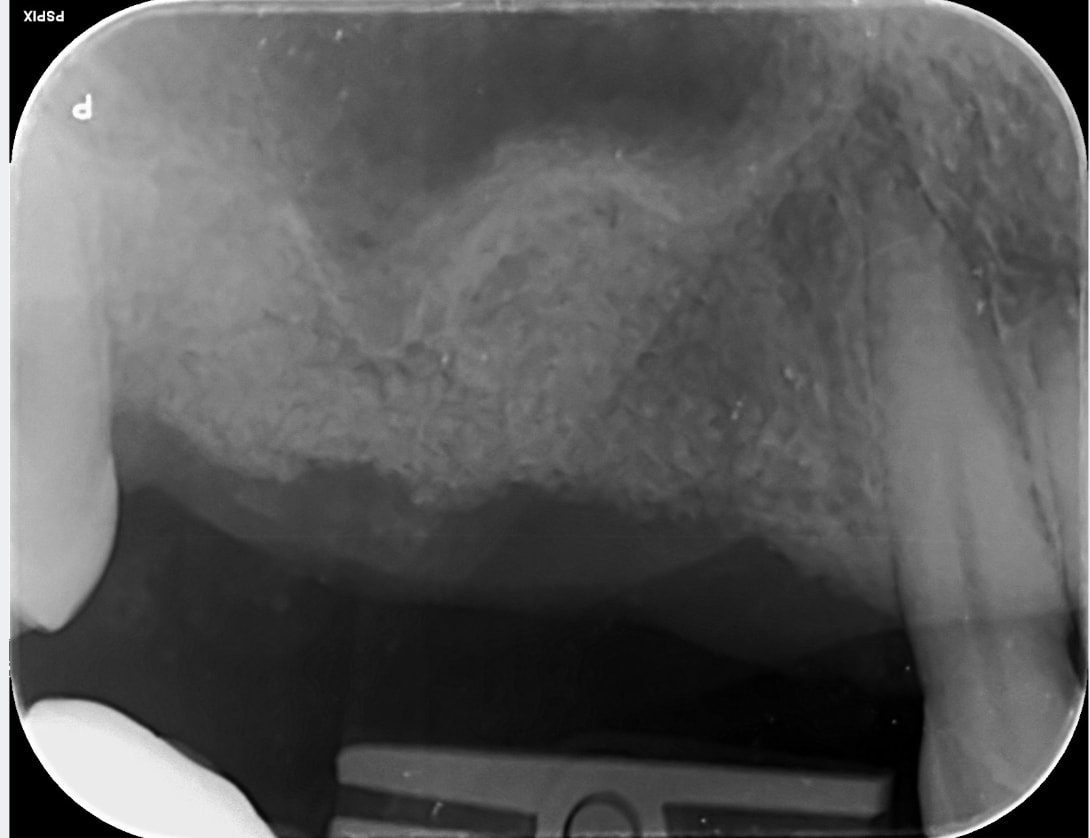

immediate post op PA.

not sure if the graft would stay, not sure if the bioguide would drop into sinus.